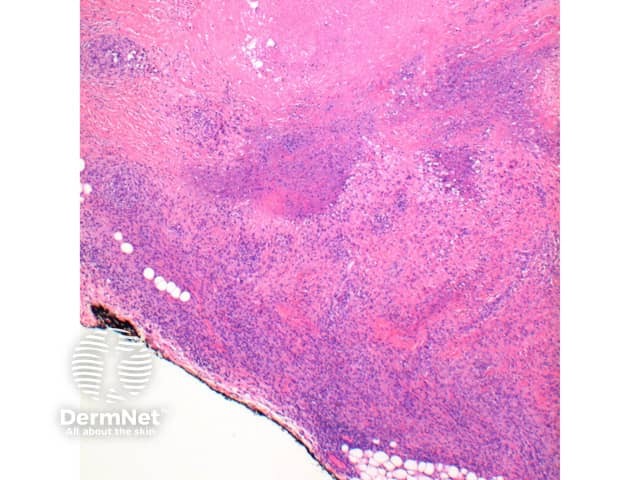

Figure 4

Subcutaneous GA: In this variant the inflammatory infiltrate is predominantly within the deep dermis and extends into the subcutaneous tissue (Figure 5, 6). Large areas of necrobiosis can be seen along with increased numbers of eosinophils (Figures 7, 8, 9).